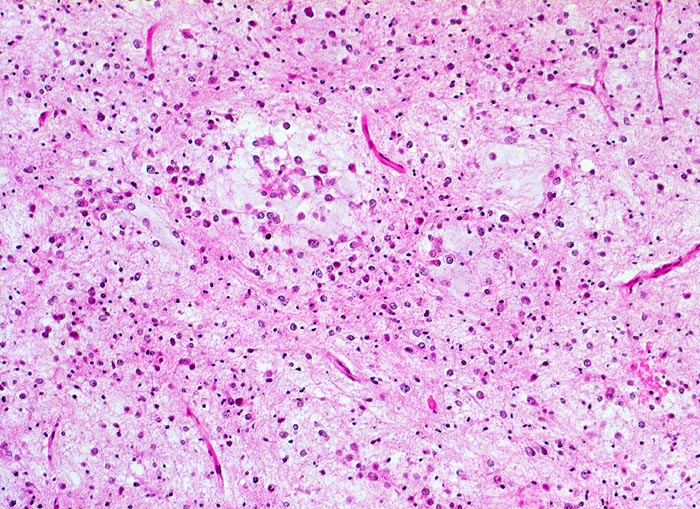

Histologisch bestehen die Oligodendrogliome aus kompakten Aggregaten runder Zellen mit deutlichen Zellgrenzen und klarem Zytoplasmasaum um einen dichten runden zentralen Kern (“Spiegelei”). Die Vakuolisierung des Zytoplasma stellt einen Fixationsartefakt dar und fällt bei Schnellschnitten als diagnostisches Hilfsmittel weg (Gefrierschnitt!). Charakteristisch sind verzweigte Kapillaren. Die Tumorzellen infiltrieren die Hirnrinde diffus und können sich bis in die Meningen ausbreiten.

Oligodendrogliome können Anteile eines Astrozytoms enthalten (Oligoastrozytom). Die Unterscheidung von reaktiven und neoplastischen Astrozyten ist im Einzelfall jedoch sehr schwierig. Oligodendrogliome umfassen ein kontinuierliches histologisches Spektrum von hoch differenzierten (WHO Grad II) bis anaplastischen malignen Tumoren (WHO Grad III). Indikatoren für das Vorliegen eines anaplastischen Oligodendroglioms sind zahlreiche Mitosen, ausgeprägte mikrovaskuläre Proliferationen und Tumornekrosen.

• Fokale mukoide/zystische Degeneration innerhalb des Tumors mit Ausbildung von Pseudozysten.

• Dichtes Netzwerk verzweigender Kapillaren.

• Tumorzellen umgeben von einem Halo ("Spiegeleier").

• Im Gegensatz zum Glioblastoma multiforme monomorphes Zellbild.